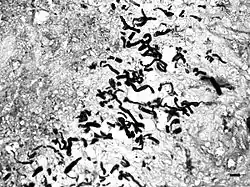

Pythium hyphae